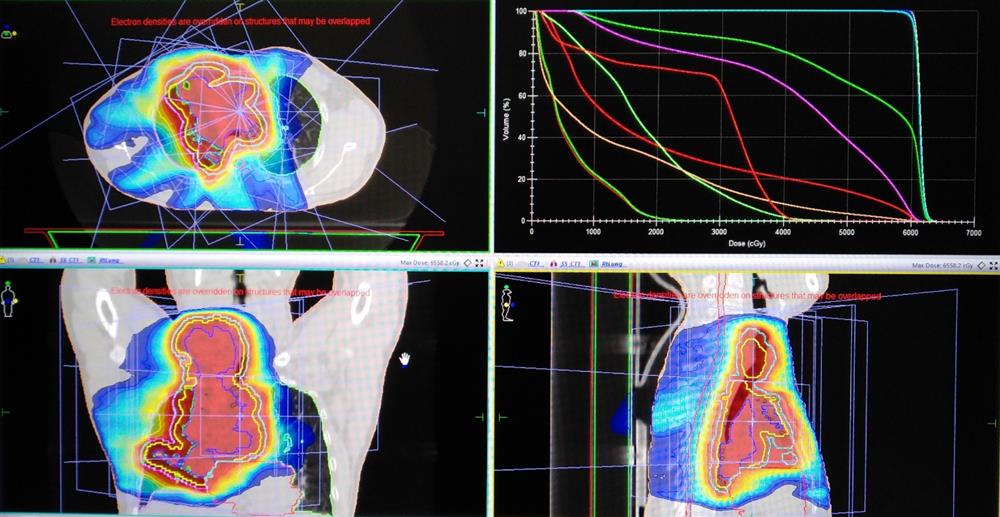

Nhằm đáp ứng nhu cầu điều trị bệnh Ung Bướu ngày một gia tăng và mang lại cơ hội sống tốt hơn cho các bệnh nhân mắc bệnh ung thư, đặc biệt là ung thư phổi, từ tháng 3/2020, Bệnh viện đa khoa Hải Dương đã đầu tư hệ thống máy xạ trị gia tốc thế hệ mới Elekta Synergy Platform của hãng Elekta - Thụy Điển, đây là thế hệ máy xạ trị gia tốc hiện đại, có nhiều mức năng lượng khác nhau, điều trị theo mọi hình dạng của khối u, có điều biến cường độ liều tia xạ dựa trên mật độ khối u nhờ vào bộ chuẩn trực đa lá và phần mềm tính liều thông minh, hiện đại, áp dụng điều trị cho hầu hết các vị trí khối u, nhiều giai đoạn ung thư. Cho đến nay đã tiến hành điều trị xạ trị cho hàng trăm bệnh nhân ung thư phổi có chỉ định điều trị đặc biệt là hoá xạ trị đồng thời mang lại nhiều giá trị cao về thời gian kiểm soát bệnh cũng như kéo dài thời gian sống thêm cho bệnh nhân.

Ung thư phổi được biết đến là một bệnh lý có tỷ lệ tử vong cao. Trước đây, thời gian sống thêm của các bệnh nhân ở giai đoạn ba trở đi chỉ dao động từ 7 đến 9 tháng, thậm chí một vài tháng nếu ở giai đoạn muộn hơn. Tuy nhiên, với việc áp dụng phác đồ hóa xạ trị đồng thời, đặc biệt được củng cố bằng điều trị đích hiện nay đã giúp thời gian sống của người bệnh có thể kéo dài đến hai năm, thậm chí 5 năm và nhiều hơn.